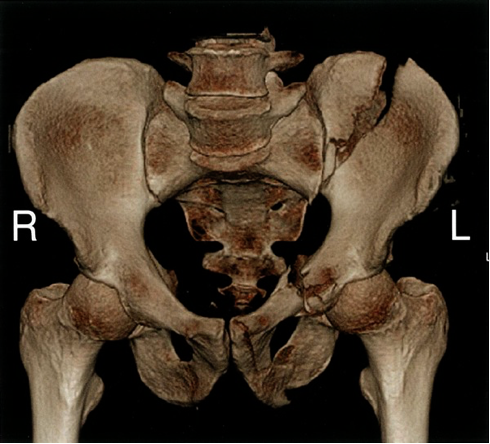

• 3D reconstruction of the bony pelvis can additionally improve surgical planning.

Left sided pelvic fractures - CT pelvis (3D reconstruction) There is an obliquely orientated comminuted fracture through the left iliac wing communicating with the left sacroiliac joint, as well as fractures of the pubis and the ischium (used mainly for surgical planning)